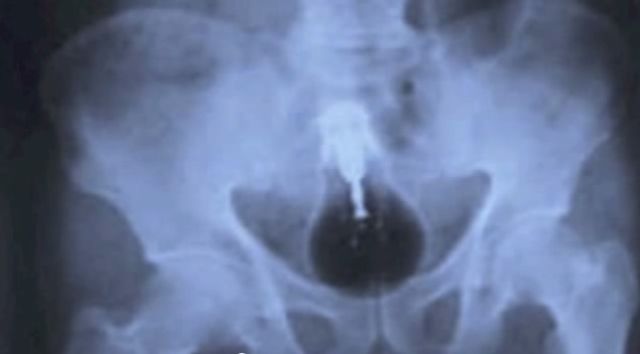

1- Une flèche